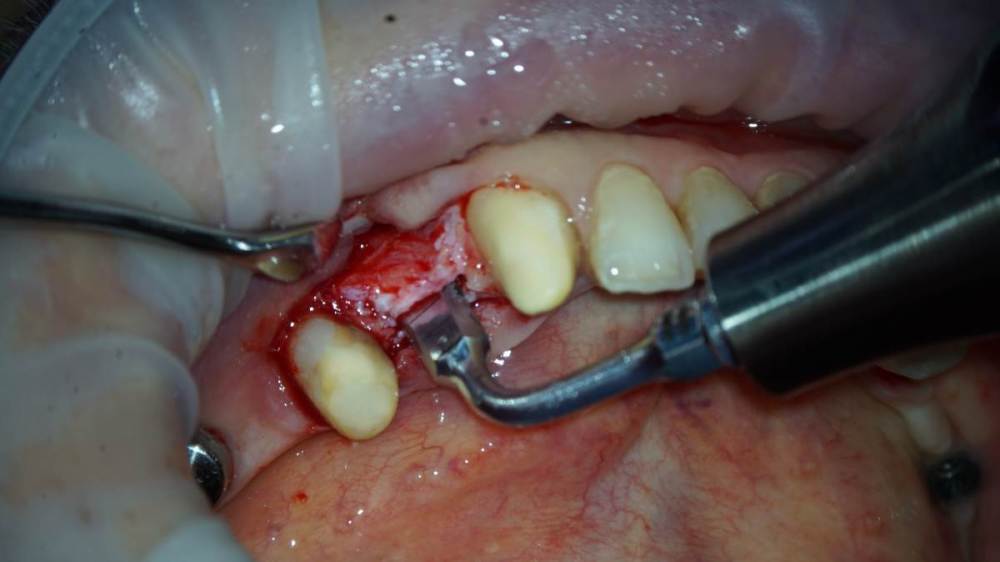

TIGER Опубликовано 10 августа, 2022 Поделиться Опубликовано 10 августа, 2022 Всем привет!Небольшой кейс с расщеплением,прошу обратить внимание на насадки,это не пилы, а остеотомы(скальпели)очень быстрое расщепление без потери тканей!Видео с операции тут 139257348_3.mp4 1 2 Ссылка на комментарий

Irouil Опубликовано 13 августа, 2022 Поделиться Опубликовано 13 августа, 2022 Эти пьезо-долотца мне тоже очень понравились, я раньше всегда работал зубастой насадкой, а как-то её не было и взял такую для синуса - потрясающе тонкий пропил 1 Ссылка на комментарий